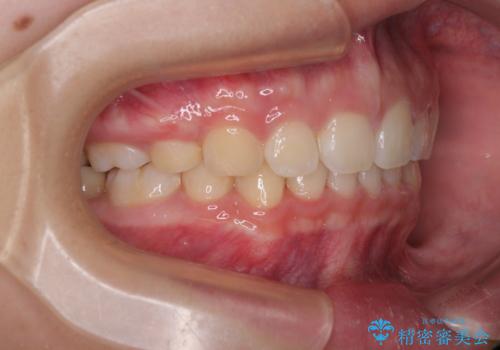

- 上顎前歯が飛び出していて唇がうまく閉じられないとのことで来院された患者様です。

くちばしのように前歯が突出していたため、口元を積極的に引っ込めるために、上下左右の小臼歯4本を抜歯することとしました。

また、上顎歯列が下顎に対して前方位に位置していたため、補助装置を用いて上顎歯列を後方に移動させ、より積極的に口元を下げるようにしました。

上下正中位置を改善するため、左下はイレギュラーに第二小臼歯を抜歯しました。そのため治療期間の長期化が予想されましたが、2年半ほどで期待通りの歯列に仕上げることができました。